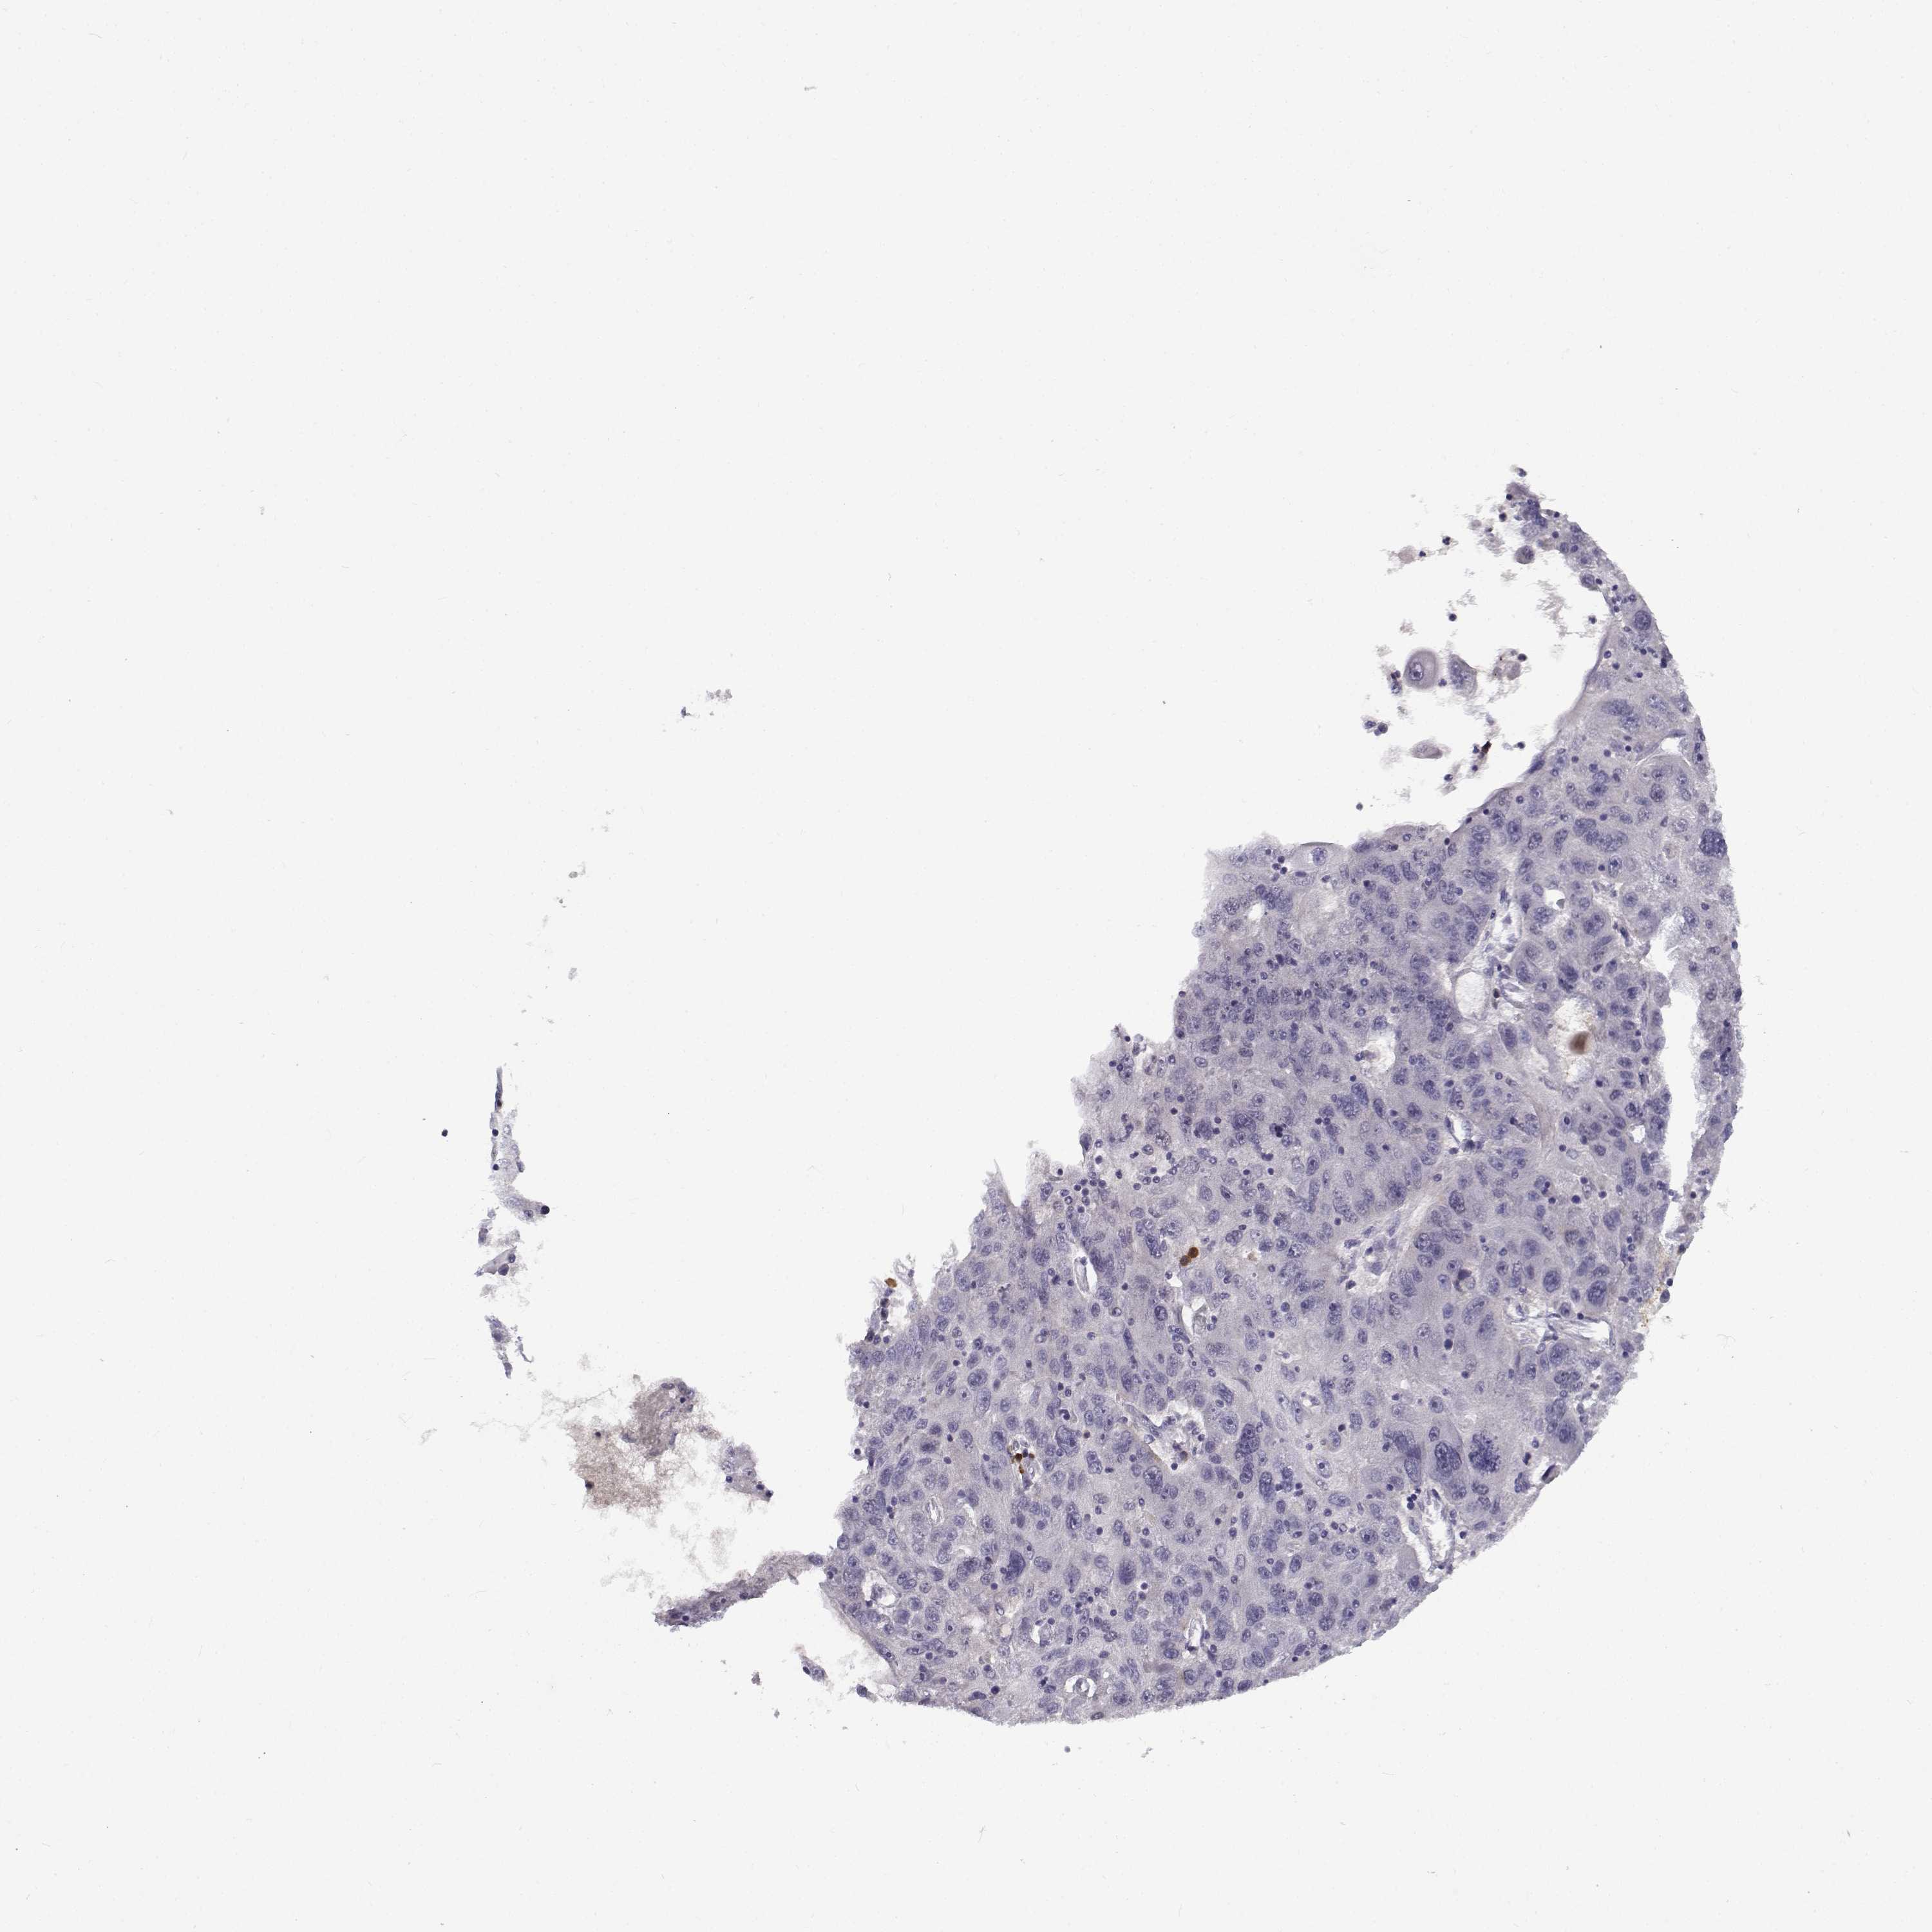

STOMACH CANCER - Protein expressioni

A mouse-over function shows sample information and annotation data. Click on an image to view it in a full screen mode. Samples can be filtered based on level of antibody staining by selecting one or several of the following categories: high, medium, low and not detected. The assay and annotation is described here.

Antibody stainingi

Antibody staining in the annotated cell types in the current human tissue is reported as not detected, low, medium, or high, based on conventional immunohistochemistry profiling in selected tissues. This score is based on the combination of the staining intensity and fraction of stained cells.

Each image is clickable and will lead to virtual microscopy that enables deeper exploration of all samples and also displays staining intensity scores, fraction scores and subcellular localization as well as patient and tissue information for each sample.

Antibody HPA069442

Staining

High

Medium

Low

Not detected

Intensity

Strong

Moderate

Weak

Negative

Quantity

>75%

75%-25%

<25%

None

Location

Nuclear

Cytoplasmic/membranous

Cytoplasmic/membranous,nuclear

Adenocarcinoma, NOS